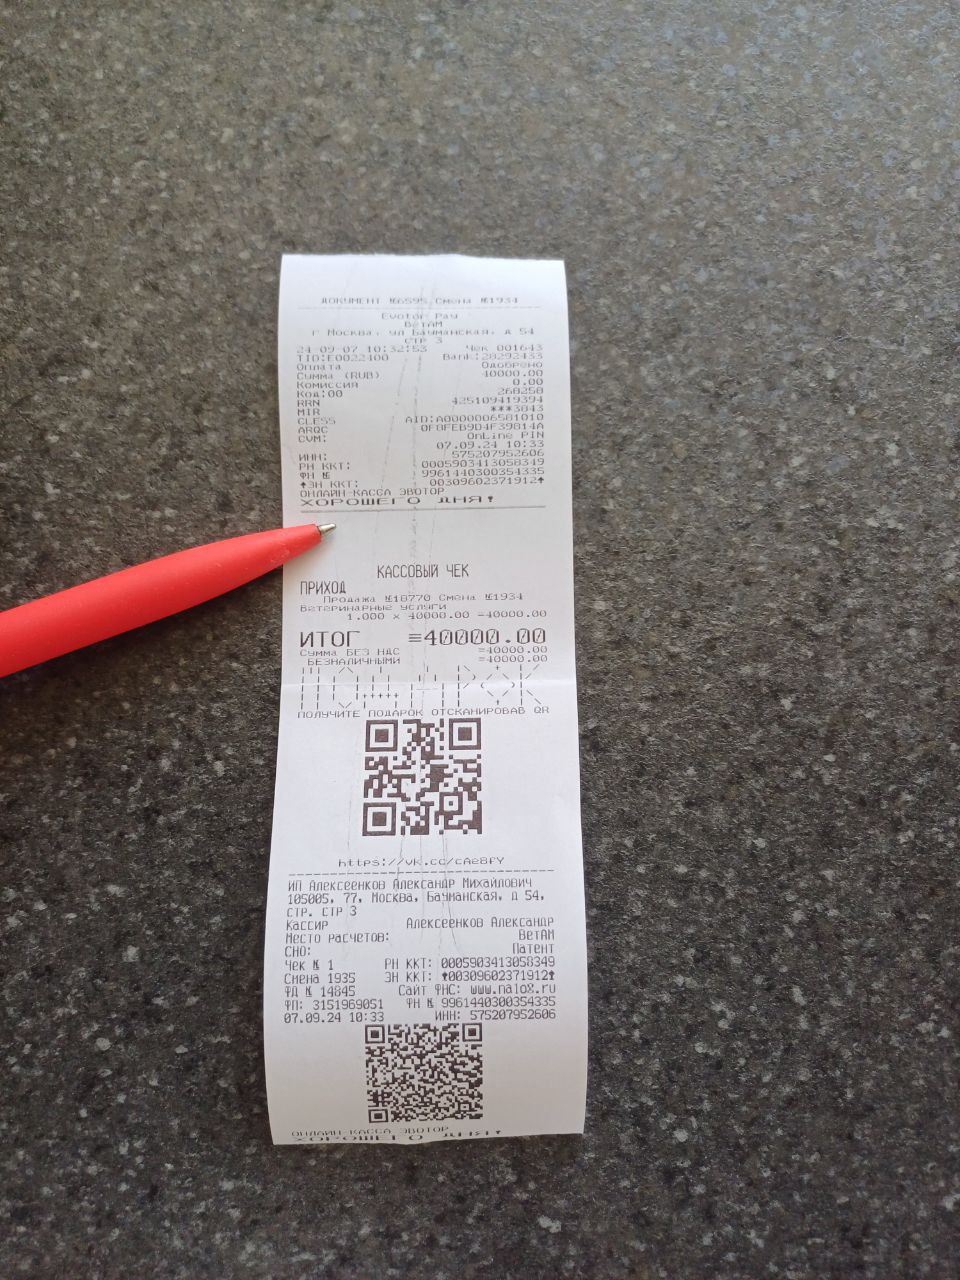

Здравствуйте,прошу откликнуться.В сентябре подобрала собачку,с поломанной лапой,сделали операцию,было смещение.Очень долго не срастался перелом.После сняли конструнцию,но около месяца назад Снова перестал становиться на лапу и сильный отек.Так как в клинике за операцию у меня все еще долг нас не примут больше,я внесла сумму 40 тысяч а долг около 20 ти еще. Предварительно нам озвучили что вероятнее всего нужно ампутировать лапу.Прошу вас кто может забрать собаку,что бы ее спасти,я не смогу сейчас осилить растраты,хоть и очень к нему привязались.Он скулит ,почти перестал кушать,я понимаю что ему больно,но не могу помочь.Прошу заберите собаку так как я не в состоянии оплатить ему лечение,выбросить на улицу не могу,усыпить подло.